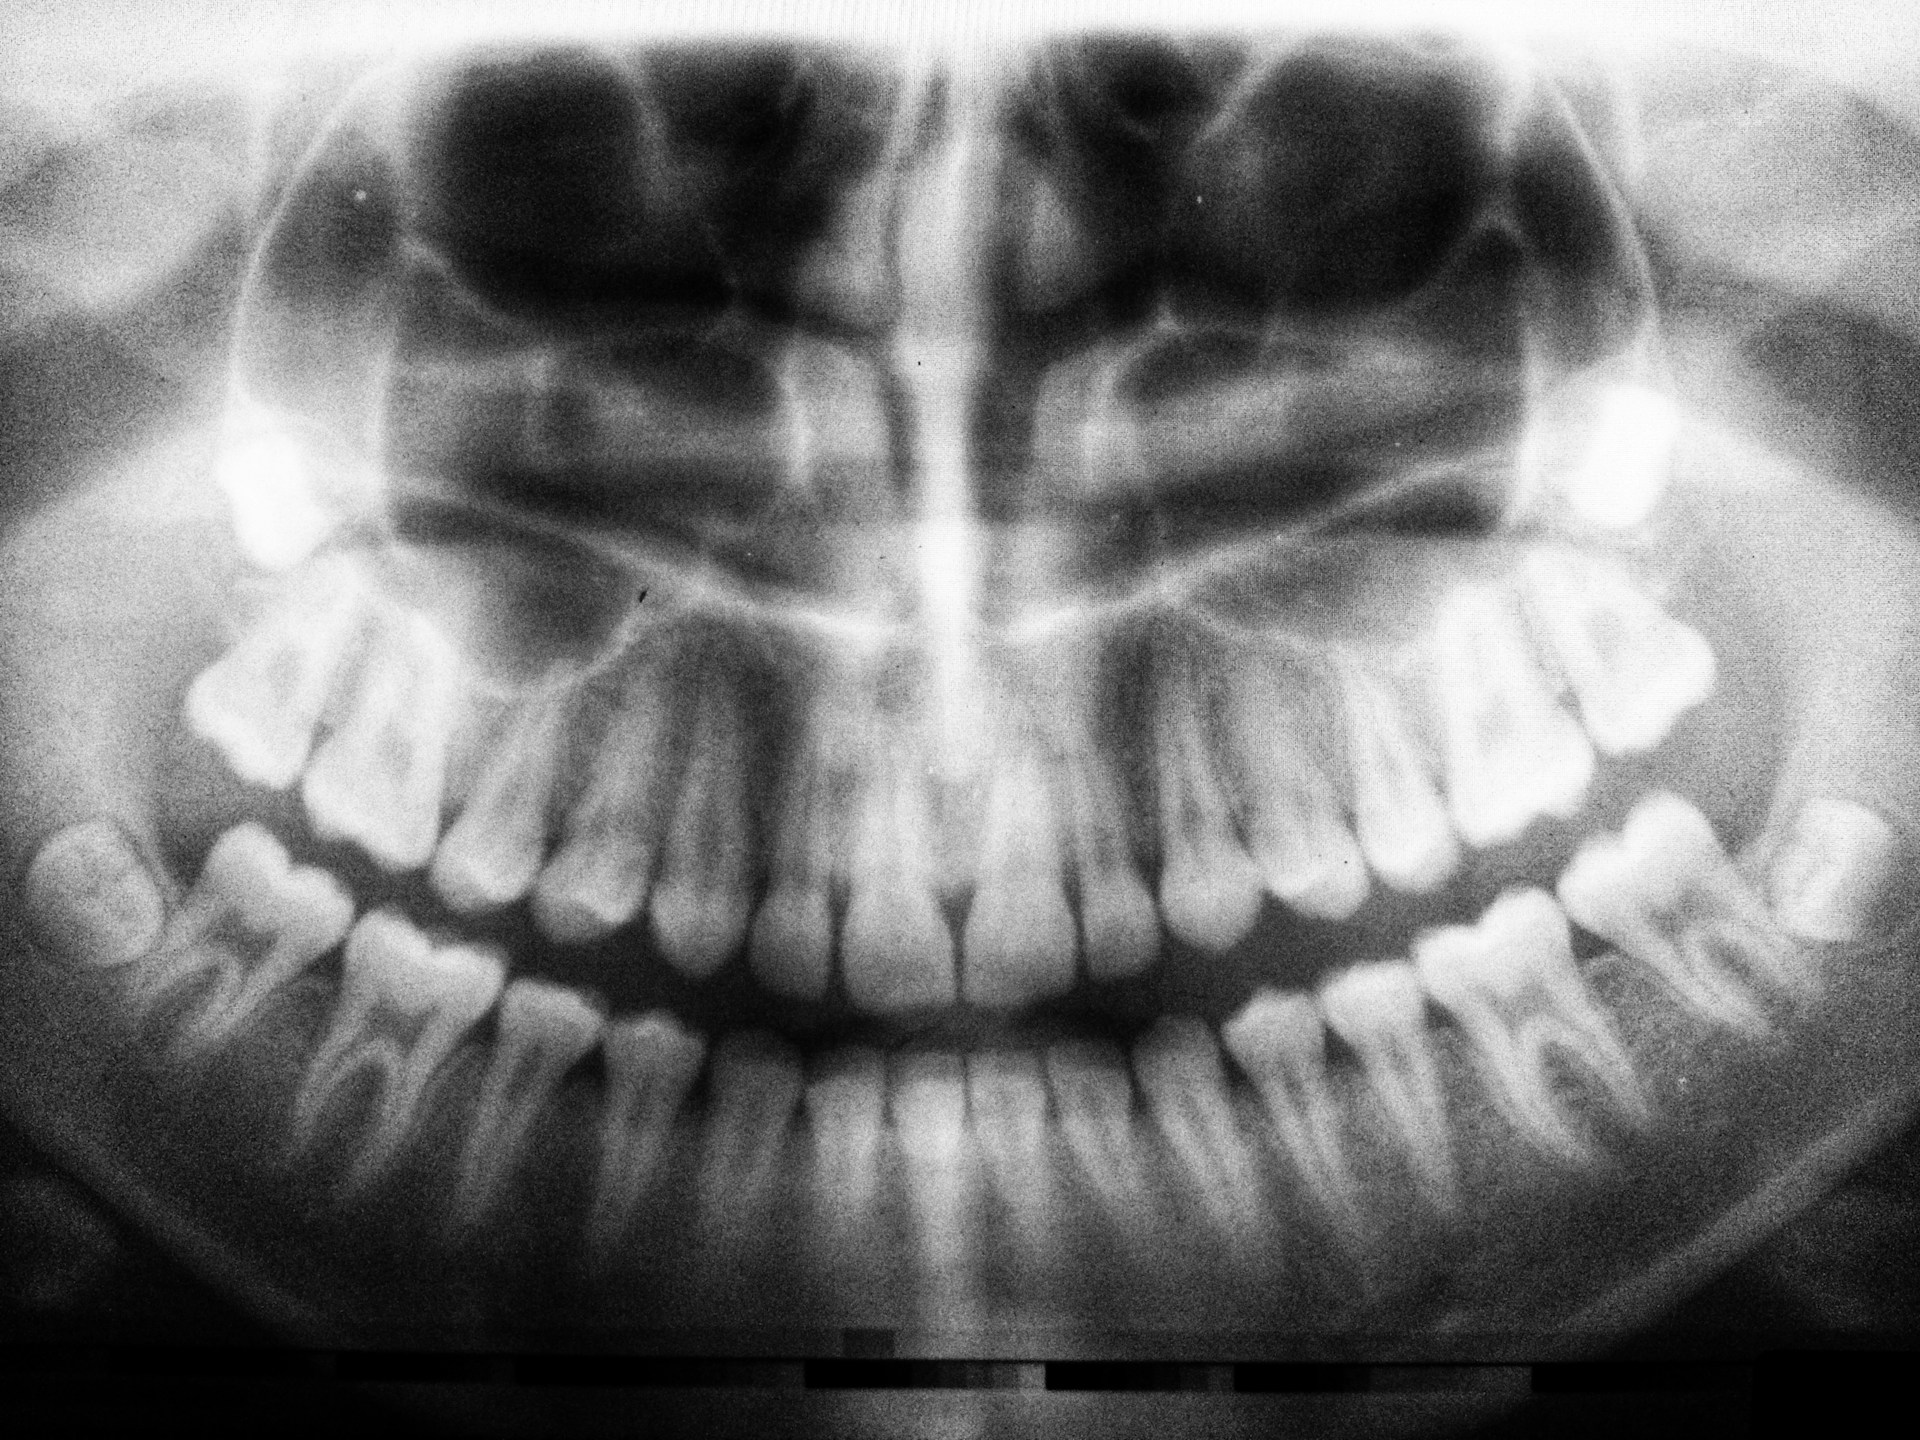

Tidak seluruh gigi bungsu harus dicabut, namun sebagian keadaan membuat pencabutan jadi opsi terbaik. Misalnya kala gigi berkembang miring, menimbulkan peradangan kesekian, ataupun mengganggu gigi di sampingnya. Dokter gigi umumnya hendak melaksanakan pengecekan rontgen buat membenarkan posisi gigi saat sebelum memastikan apakah pencabutan dibutuhkan ataupun tidak.

Banyak permasalahan gigi bungsu hadapi impaksi, ialah keadaan kala gigi tidak dapat berkembang sempurna sebab terhalang tulang ataupun gigi lain. Apabila dibiarkan, impaksi dapat menimbulkan peradangan, bau mulut, sampai kehancuran pada gigi di sebelahnya. Seperti itu kenapa pengecekan teratur ke dokter gigi sangat berarti buat mengenali keadaan gigi bungsu semenjak dini.